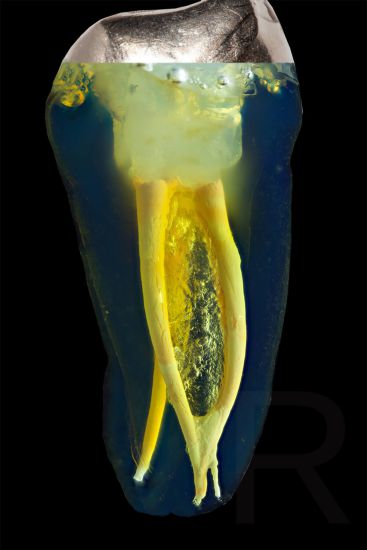

Das Verfahren, Zähne in durchsichtige Präparate zu überführen ist schon über 100 Jahre alt. Aber erst durch die Weiterentwicklung der alten Technik und die Kombination mit moderner Fotografie sowie der Entwicklung eines geeigneten Gefäßes zur Fotografie ist es meinem Vater Dr. Holm Reuver gelungen, einzigartige Bilder vom Inneren der Zähne aufzunehmen.

Die Bilder sind in verschiedenen Größen wählbar und auch als POPART-Variante erhältlich. Sie sind hervorragend geeignet für die Beratung von Patienten vor endodontischen Behandlungen, aber auch ein beliebter Eyecatcher im Wartezimmer. Außerdem haben die Bilder einen bedeutenden Stellenwert für die Erforschung der Pulpatopografie und für die Lehre im Bereich der Endodontie.